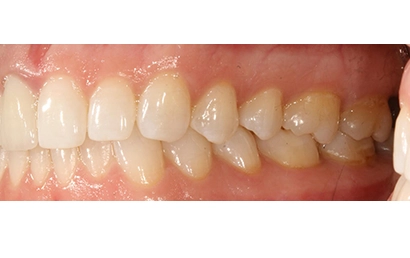

Chief Complaint: The patient presented with an upper right lateral incisor exhibiting mobility. Further examination revealed a history of endodontic treatment combined with root fracture.

Intraoral Assessment: Porcelain crowns were present on the upper right lateral and central incisors. The upper right central incisor displayed a root canal treatment, a periapical lesion, and a root fracture accompanied by discolored and inflamed gingiva. The lateral incisor had a periapical lesion deemed untreatable by the endodontist. The gingival papilla was receding between these teeth, manifesting as a visible black triangle.

Intraoral pictures of the initial condition